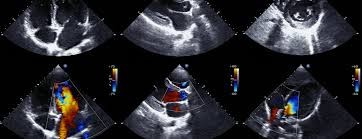

Day 1 focuses on FUSIC heart, with lectures on basic heart ultrasound, heart ultrasound in shock, volume assessment and lectures on assessing Left and Right heart. Plenty of Hands on workshops on volunteers and real patient, taught by experienced faculty from cardiology and critical care.